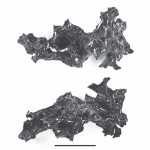

Η έκρηξη του Βεζούβιου το 79 μ.Χ μετέτρεψε τον εγκέφαλο ενός θύματος σε… γυαλί

Σε γυαλί μετατράπηκε ο εγκέφαλος ενός 25χρονου άνδρα που βρήκε τραγικό θάνατο στην πόλη Ηράκλειο (Ερκουλάνουμ) της Ιταλίας, κοντά στην Πομπηία, κατά την τρομερή...